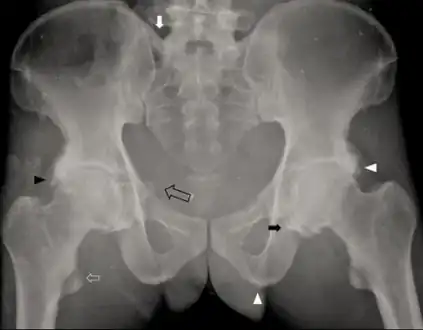

a-c)Brain computed tomography shows diffuse symmetric parenchymal calcifications Individual with idiopathic hypoparathyroidism-diffuse osteosclerosis, capsular ossification around bilateral hip joints arrow, ossification of bilateral iliolumbar ligaments arrow, irregular bony excrescences arrowhead, subtle calcification of the right sacrospinous ligament open arrow

Individual with idiopathic hypoparathyroidism-diffuse osteosclerosis, capsular ossification around bilateral hip joints arrow, ossification of bilateral iliolumbar ligaments arrow, irregular bony excrescences arrowhead, subtle calcification of the right sacrospinous ligament open arrow